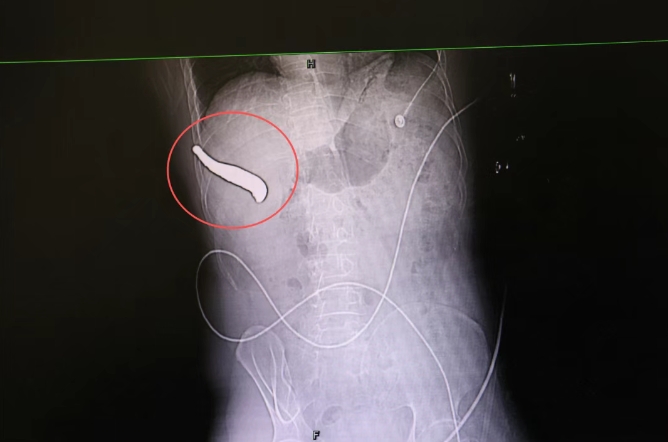

惊险!长约15cm的金属钻头,穿透腹腔刺破肝脏…… 翔安区融媒体中心 业翔民安 2025年09月05日 22:19 福建